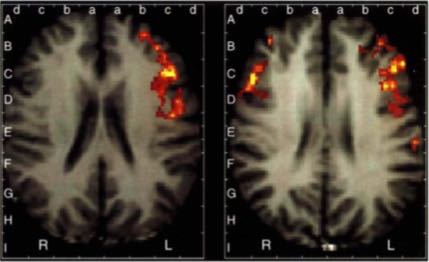

This brings us back to the hard problem of consciousness research. The advent of neuroscience has provided us with genuine insights into how the brain processes information, including sensory and cognitive tasks associated with conscious attention and resting, or meditative states. We can then associate a variety of conscious states with activity, either by electroencephalographic portraits of brain waves, by functional magnetic resonance images of blood flow to specific regions, or by positron emission tomography of radioactive glucose, and even by invasive studies of actual neurons and connections in animals. Various researchers can then attempt to deduce how these excitations give rise to the conscious experience, e.g. by the activities of certain frequency bands, such as gamma from 30-100 Hz.